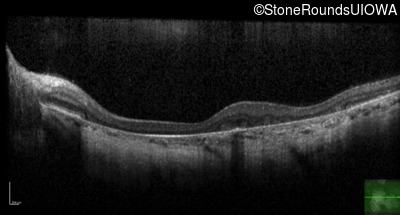

Optical Coherence Tomography - Right - 20/25 -2 sc

Exemplar / OCT Stack